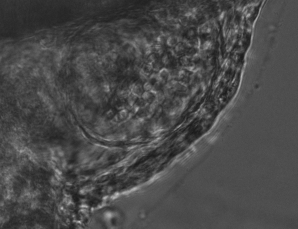

However, throughout development the zebrafish heart changes in size, shape and beat rate, causing difference between live brightfield images and the original reference heartbeat. These differences lead to errors in the prospective optical gating that will get ever larger when capturing over long, developmental time periods (fig. 1).

The combination of prospective optical gating for real-time phase matching and prospective optical gating for long-term phase locking allow us to capture in phase images over extended periods of times. Figure 4 demonstrates this phase locking over 18+ hours across a key developmental phase - heart looping.